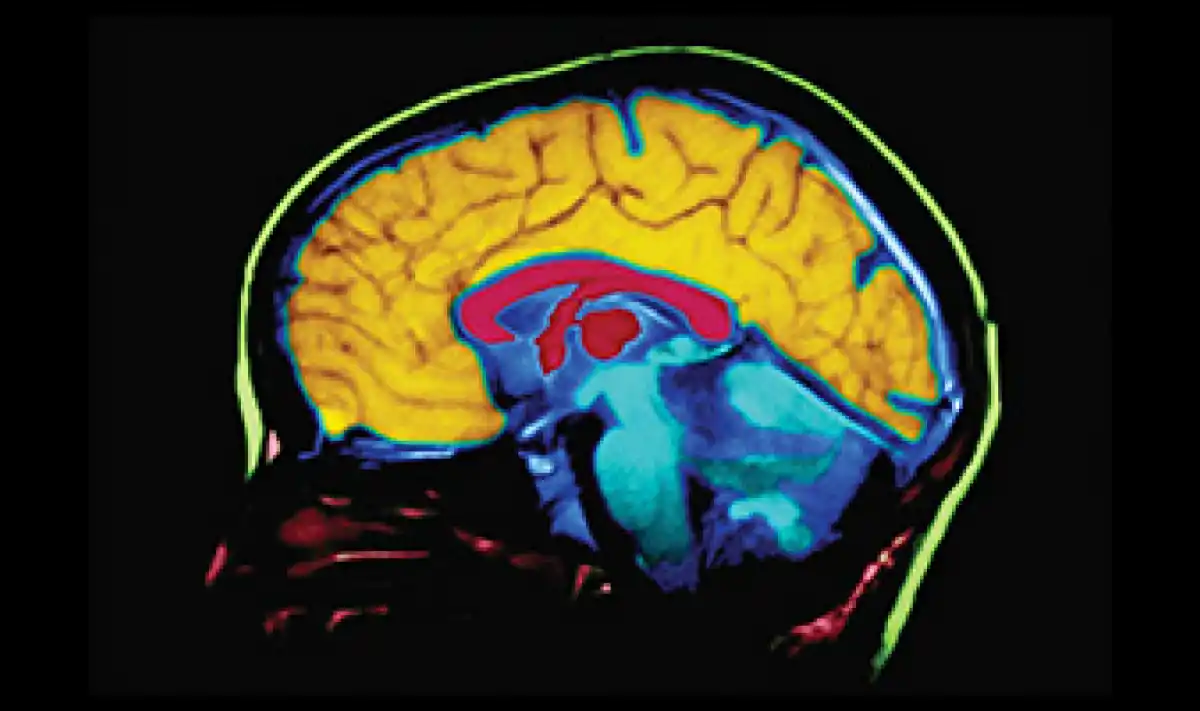

Los científicos plantean la hipótesis de que el uso a largo plazo de estos antiinflamatorios puede reducir la acumulación de placas beta amiloide en el cerebro, que siguen siendo un sello distintivo de la demencia y la enfermedad de Alzheimer. Sin embargo, los resultados excluyeron a las personas que eran portadoras del gen APOE-ε4, un factor de riesgo conocido para el Alzheimer.